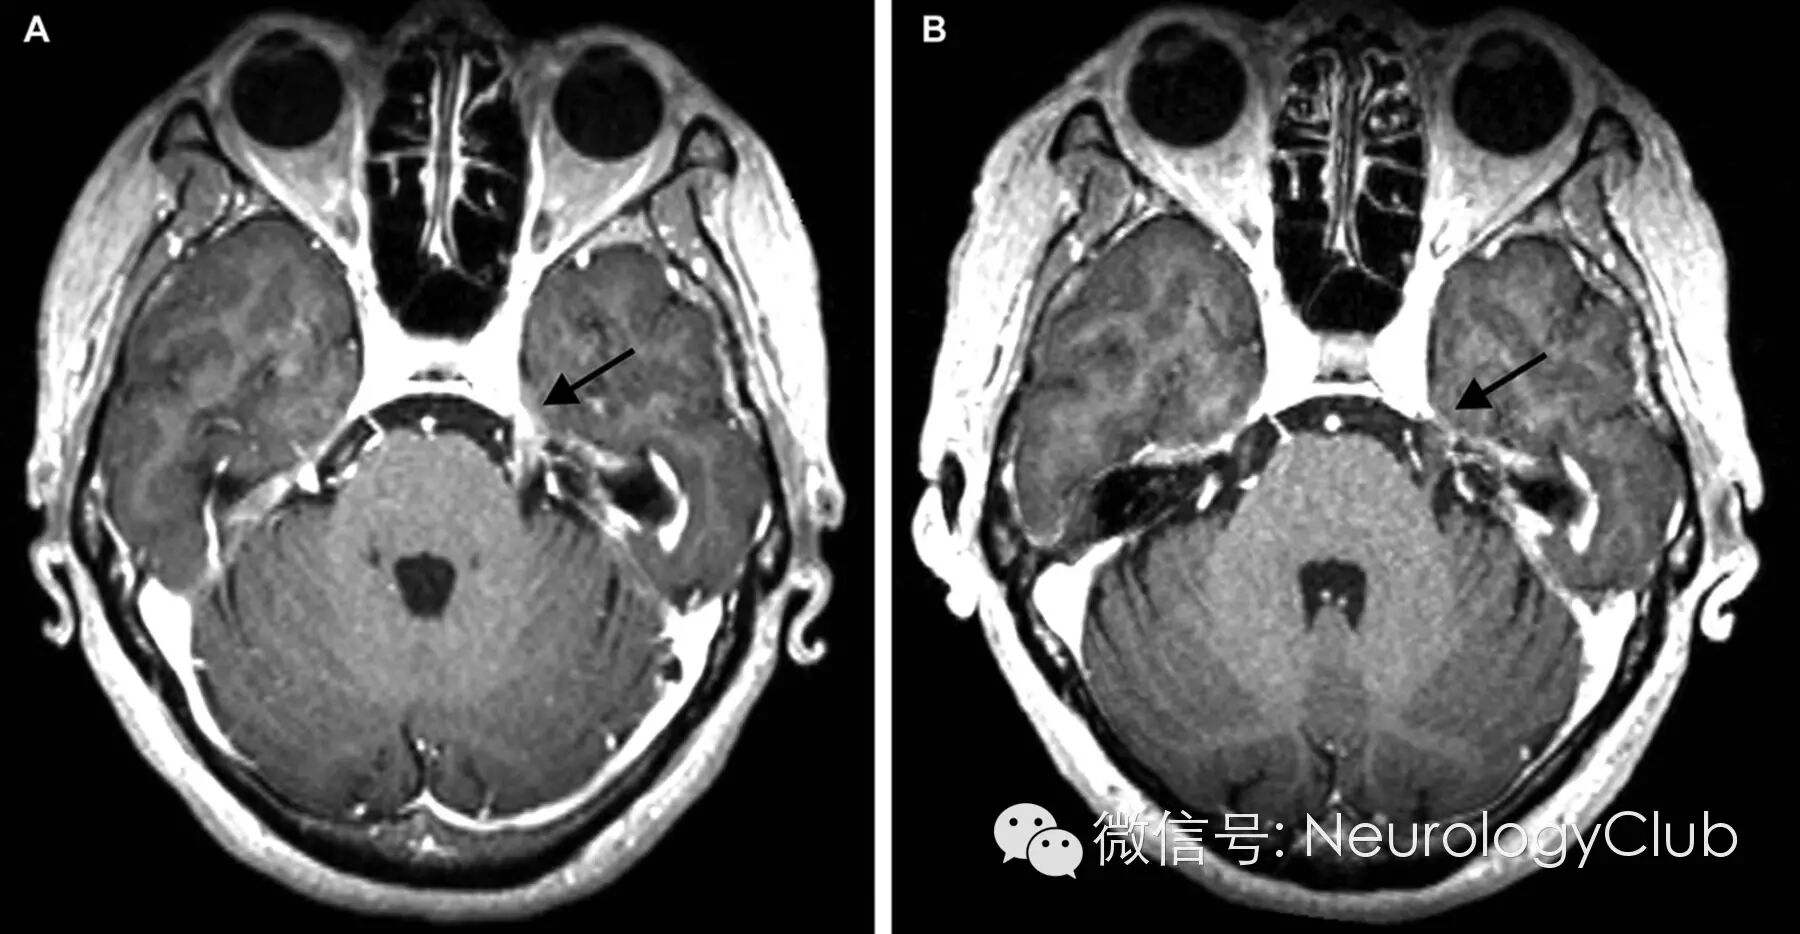

盆腔MRI提示左侧腰骶神经根、丛和坐骨神经异常增粗强化信号(图1 A,B);头颅MRI提示左侧三叉神经强化信号(图2 A);全身PET检查提示双侧臂丛,左侧腰骶神经根和坐骨神经代谢增加。

(图2:T1增强磁共振提示三叉神经沿脑池部分异常强化[A],化疗后好转[B])